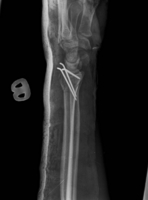

Van valakinek tapasztalata csuklósérüléssel kapcsolatban? Az orsócsontom tört 2 helyen és a sajkacsontom. 3 szeggel rögzítették az orsót, a sajkát nem kellett.

Minden érdekel, gyógyulás, rehab, erősítés, majdani védelem, orvosok, kórházak. Esztergomban műtötték, dr. Kőváry Tamás. Műtötte már Borkát, meg Léczet, elméletileg van esély, hogy teljesen helyrejön...